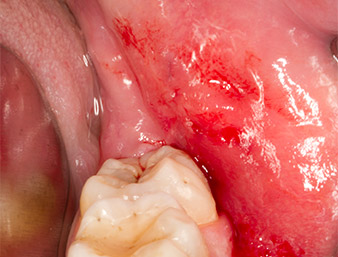

Tras una anestesia local y por conducción, el campo quirúrgico se abrió mediante los tejidos blandos para tener un acceso bucal-retromolar y se dejó expuesto (figura 3).

corte surcular

Imagen 3: El corte surcular comienza en el centro del diente 36, con alargamiento distal en la rama ascendente.

El tejido situado por encima del resto radicular no se había osificado por completo y constaba en su mayor parte de un tejido granulado con alteraciones inflamatorias (figura 4).

tejido granulado

Imagen 4: Dos ganchos de Langenbeck y un raspador según Prichard exponen el campo quirúrgico. Se distingue un tejido granulado de la primera osteotomía que no ha cicatrizado en su totalidad.